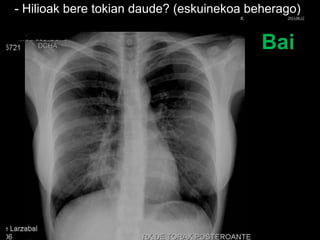

- Hilioak bere tokian daude? (eskuinekoa beherago)

Bai